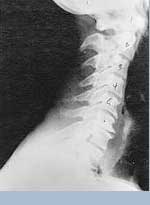

Phase One Subluxation Degeneration is seen in subluxations that have been present for up to twenty years. This phase is characterized with a loss or change in the normal curve in the spine. On this example you can see that the normal forward (lordotic) curve is lost. This spine even has developed a reverse curve in the neck. The disc spaces have also begun to exhibit a slight change in shape. One good point is that the bodies of each of the vertebrae (the square part in front) still exhibits clean clear borders. Segmental motion may be abnormal but overall motion is probably not affected. Chiropractic reconstructive care for a phase one can take from 6 to 18 months. More than 80% of people with Phase One Subluxation Degeneration have no pain. Therefore, if left uncorrected, phase one continues to progress with time until it eventually reaches the next phase.